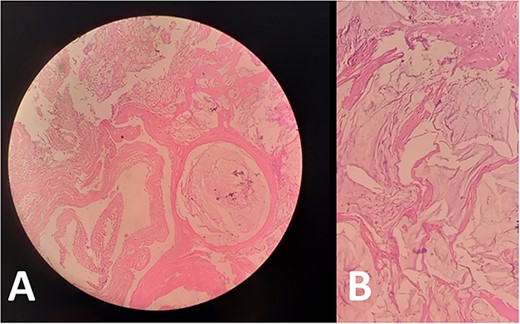

The pathology report prescribed pools of mucus without malignant cells, which is indicative of PMP (Fig. 3).

Biopsies from (A) peritoneum and (B) omentum showed acellular mucin consistent with PMP. No mucinous, degenerative or tumor cells are seen.